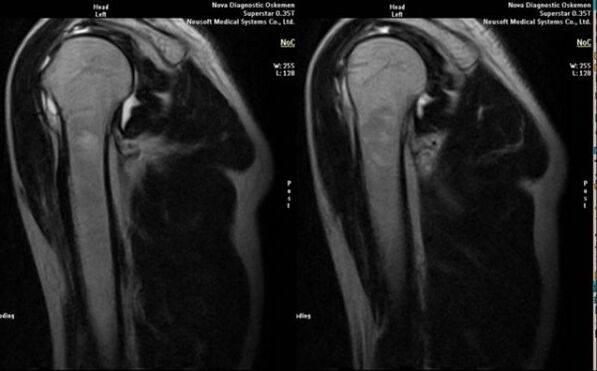

- MRT- und CT-Scan;

Zu den Anzeichen, die direkt auf die Entwicklung einer Arthrose hinweisen, gehören das Auftreten einer deutlichen Verengung des Gelenkraums, Sklerose subknorpeliger Strukturen, Ausdünnung der Chondrozytenschicht selbst, das Auftreten von Osteophyten und die Ablagerung von Salzkristallen in der intraartikulären Flüssigkeit.